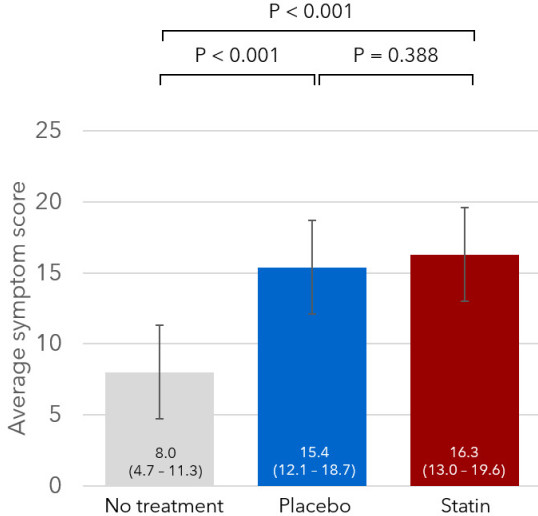

James was joint first author on the SAMSON trial, published in the New England Journal of Medicine. This novel "N-of-1" trial used smartphones to assess daily symptoms in patients who were previously unable to take statins, and showed that 90% of the symptom burden our patients suffer from taking statins is also present when they take placebo. The trial received widespread international interest (BBC; Daily Mail).